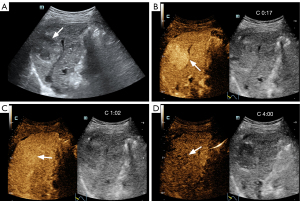

In the CEUS findings, necrosis was identified in six of the HCC-predominant lesions and in one of the ICC-predominant lesions. Among the HCC-predominant lesions, 21 lesions were classified as LR-M based on the presence of at least one of the related CEUS LI-RADS criteria (version 2017), which showed the following distribution: rim-like APHE in eight lesions, early washout in 19 lesions, and marked washout in 19 lesions. Among the ICC-predominant lesions, nine were classified as LR-M (Figure 2) and one as LR-TIV. Rim-like APHE was observed in five lesions, early washout in 10, marked washout in six, and portal vein thrombus enhancement in one. Homogeneous or heterogeneous APHE exceeding 10 mm in diameter, along with mild and late washout, was observed in 12 HCC-predominant lesions and one ICC-predominant lesion, and these were categorized as LR-5 (Figure 3).